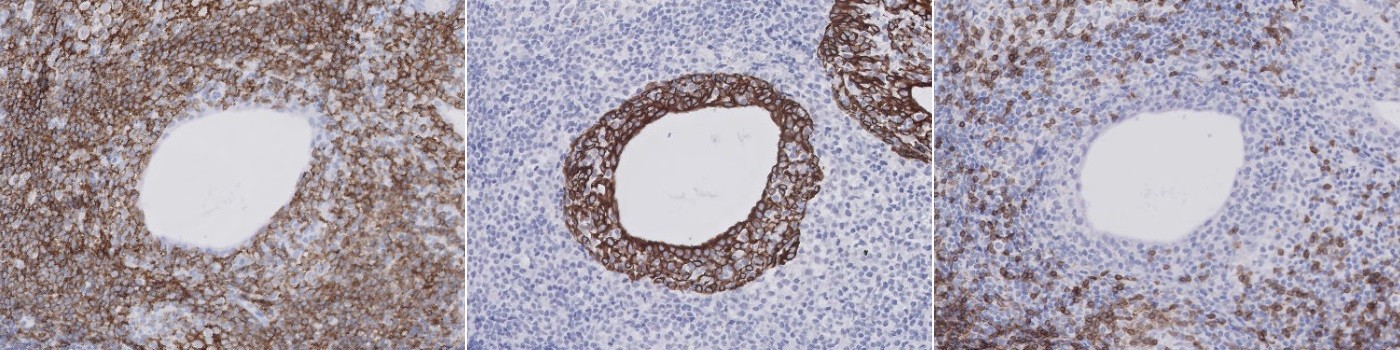

Alignment of 3 serial tissue section images with different stains (CD3, CK, CD20) referred to as Virtual Triple Staining (VTS).

Evaluation of the lymphocytic infiltration is relevant in the study of the pathogenesis and outcome of Sjögren’s syndrome, see [1] and [2]. A manual evaluation of the infiltration is challenging, especially if it should be limited to the striated ducts of salivary gland tissue. This APP allows for automatic quantification of CD3 positive T-cells and CD20 positive B-cells within CK positive ducts.

The APP is based on a virtual triple staining (VTS) technique where serial tissue sections with different stains are co-registered and analyzed as a single slide for quantification. The co-registration is referred to as alignment and is carried out using the Tissuealign™ module. The order of alignment is: CD3 section followed by CK section followed by CD20 section.

The ducts are found by use of the HDAB-DAB color deconvolution band and an intensity-based threshold classifier. The configuration for quantification of CD3 positive cells works within the automatically outlined ducts. Detection of CD3 positivity is based on the HDAB-DAB color deconvolution band and separation of positive cells are based on application of a watershed algorithm assisted by a polynomial local linear filter applied to the red color band. The CD20 positive cells are detected by characterization of the stain in the cytoplasm of the cells based on the HDAB-DAB color deconvolution band. A polynomial blob filter and a polynomial local linear filter similar to that used for the CD3 cell quantification protocol assists the cytoplasm detection.